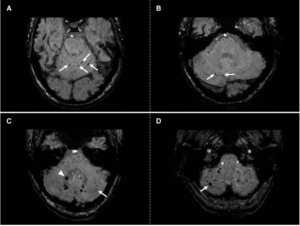

- PET/CT: sfrutta la rara emissione di positroni (circa 32 per milione di decadimenti). Nonostante il basso segnale, la moderna tecnologia PET/CT, specialmente con tempo di volo (TOF), consente un’imaging quantitativo di alta qualità. Offre una risoluzione spaziale e una capacità di quantificazione superiori rispetto alla SPECT. Per ottenere immagini di buona qualità, si raccomandano tempi di acquisizione di almeno 15 minuti;

- SPECT/CT da Bremsstrahlung: rileva i fotoni di “frenamento” prodotti dall’interazione delle particelle beta con i tessuti. Sebbene sia più accessibile, la qualità dell’immagine e l’accuratezza quantitativa sono inferiori rispetto alla PET/CT.

L’Olmio-166 permette un imaging multimodale diretto:

- SPECT/CT: la co-emissione di fotoni gamma a 81 keV consente un’acquisizione diretta della distribuzione delle microsfere. L’imaging presenta sfide tecniche, come lo scatter dei fotoni ad alta energia e il rischio di “dead time” del detector a causa dell’elevata attività iniziale. Per questo motivo, l’acquisizione è generalmente raccomandata tra 2 e 5 giorni dopo il trattamento;

- RMN: l’Olmio-166 possiede proprietà paramagnetiche che ne consentono la visualizzazione e la quantificazione tramite Risonanza Magnetica. I vantaggi includono un’alta risoluzione spaziale e l’assenza di radiazioni ionizzanti. Tuttavia, la presenza di artefatti da suscettibilità magnetica può limitarne l’applicazione in prossimità di aria o clip metalliche.